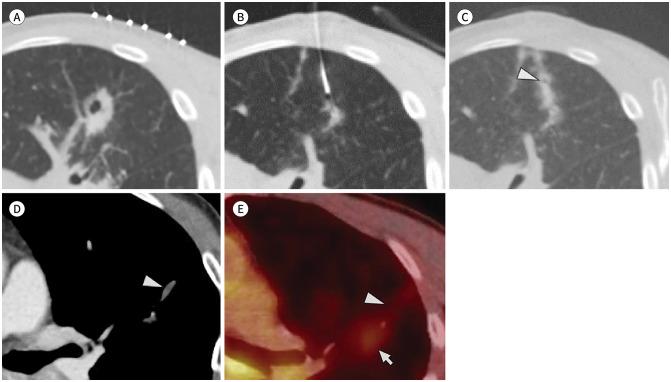

CT-guided percutaneous transthoracic needle biopsy (PTNB) plays a key role in the diagnosis of pulmonary abnormalities. Although the procedure is considered safe and effective, there exists a potential for complications, such as pneumothorax, hemorrhage, hemoptysis, air embolism, and tumor seeding. However, pneumatoceles after CT-guided PTNB have been rarely reported. Herein, we report two cases of pneumatoceles that developed immediately after PTNB for primary lung cancer. A pneumatocele filled with hematoma should be considered in cases with a newly developed nodule along the needle tract during short-term follow-up CT after PTNB.

CT引导下经皮经胸针吸活检(PTNB)在肺部异常诊断中起着关键作用。尽管该操作被认为是安全有效的,但仍存在并发症的可能性,如气胸、出血、咯血、空气栓塞和肿瘤种植。然而,CT引导下PTNB后发生肺气囊的情况鲜有报道。在此,我们报告两例原发性肺癌PTNB后立即出现的肺气囊病例。在PTNB后的短期随访CT中,沿针道出现新的结节时,应考虑为充满血肿的肺气囊。